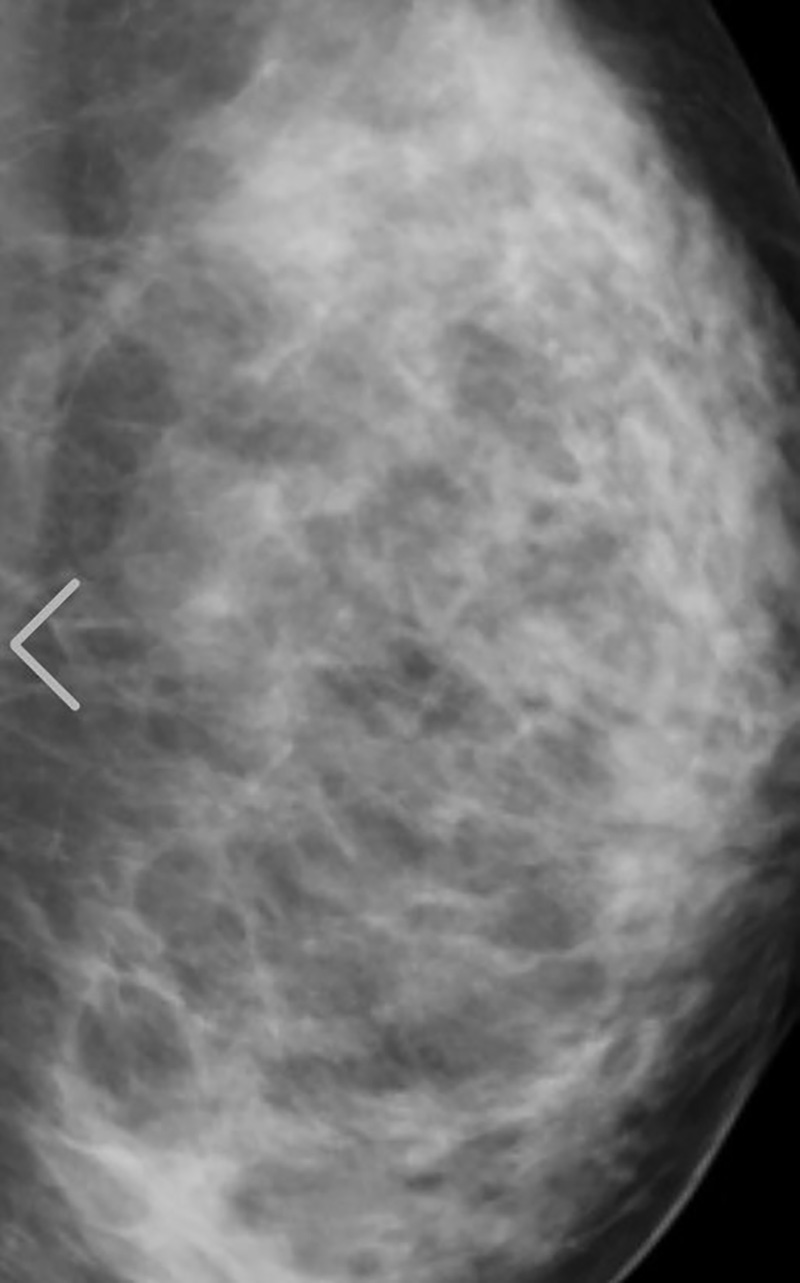

ด้วยกระแสลือหนักเข้า ทำให้ในที่สุดสาวฟูมินะ ซูซูกิ ตัดสินใจ ออกมาเปิดภาพเอกซเรย์ทรวงอกให้เห็นกันแบบเต็ม ๆ ตา จะได้รู้กันไปเสียที ว่าใหญ่ ๆ ที่เห็นอยู่นี้ คือขอแท้แม่ให้มา ธรรมชาติล้วน ๆ โดยมีการโพสต์ภาพลงในโซเชียลมีเดียต่าง ๆ ของเธอทั้งอินสตาแกรมและทวิตเตอร์ เมื่อวันที่ 14 กันยายน 2565 พร้อมแคปชั่นว่า

"รูปเอกซเรย์เต้าของฉัน ! 555 นี่พิสูจน์ได้หรือยังว่าหน้าอกของฉันคือธรรมชาติ ? ครั้งแรกเลยนะเนี่ยที่ฉันออกมาโชว์กระดูกกับไขมันให้ผู้คนได้เห็น"

ก็บอกได้เลยว่าลงทุนเอกซเรย์ให้เห็นกันเต็มตาขนาดนี้ หลาย ๆ คนก็คงจะหายคาใจกันเสียที ว่าความงามของเธอคนนี้ธรรมชาติหรือไม่